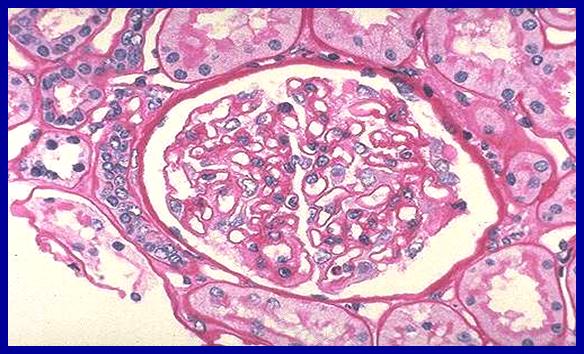

病理组织学检查可见脑组织异常,有嗜苏丹性脑白质营养不良;肝硬化,肝内胆和这发育不良;多囊肾;动脉导管未闭、卵圆孔未闭等心脏畸形;肺不张及含铁血黄素沉着;胰岛细胞增生,胸腺发育不良。